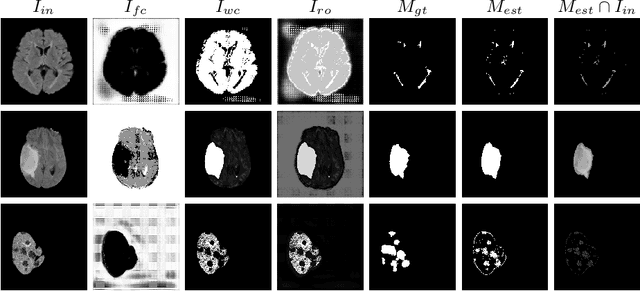

Abstract:Brain extraction is a fundamental step for most brain imaging studies. In this paper, we investigate the problem of skull stripping and propose complementary segmentation networks (CompNets) to accurately extract the brain from T1-weighted MRI scans, for both normal and pathological brain images. The proposed networks are designed in the framework of encoder-decoder networks and have two pathways to learn features from both the brain tissue and its complementary part located outside of the brain. The complementary pathway extracts the features in the non-brain region and leads to a robust solution to brain extraction from MRIs with pathologies, which do not exist in our training dataset. We demonstrate the effectiveness of our networks by evaluating them on the OASIS dataset, resulting in the state of the art performance under the two-fold cross-validation setting. Moreover, the robustness of our networks is verified by testing on images with introduced pathologies and by showing its invariance to unseen brain pathologies. In addition, our complementary network design is general and can be extended to address other image segmentation problems with better generalization.